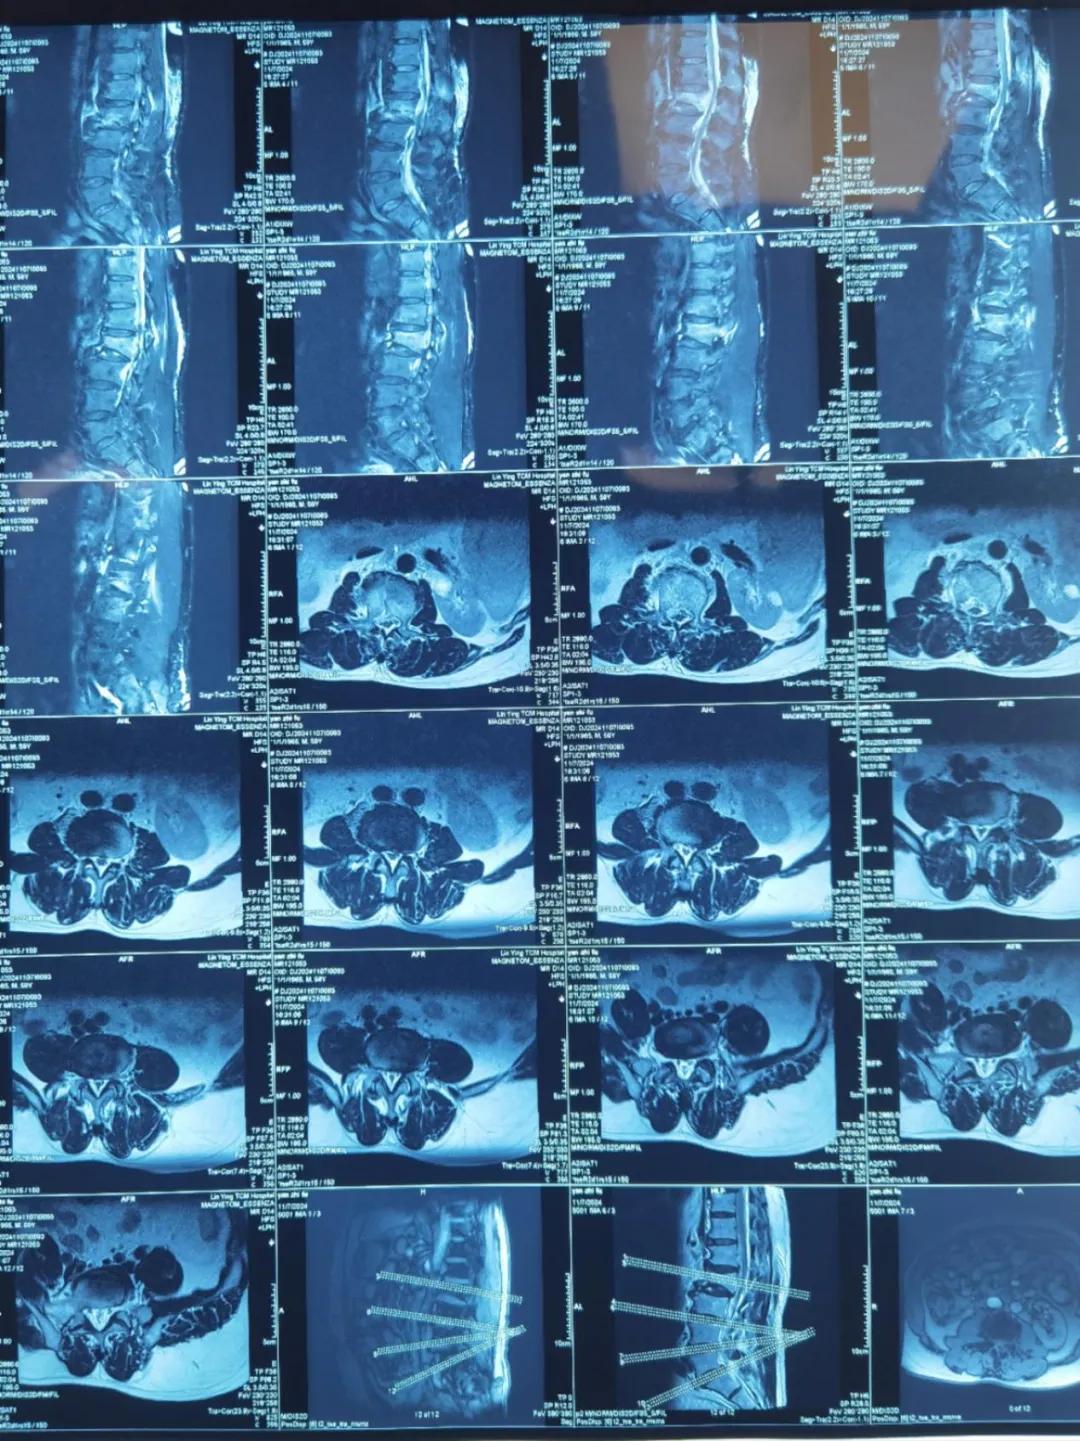

“醫(yī)生,這是之前的檢查結(jié)果,還需要再做檢查嗎?”閆大叔從外院轉(zhuǎn)來被推進(jìn)智能微創(chuàng)骨科。幾天前,他在老家的中醫(yī)院進(jìn)行了抽血檢驗(yàn)和磁共振檢查,因?yàn)檠蹏?yán)重、行動(dòng)不便檢查過程也十分不易。

智能微創(chuàng)骨科副主任李鵬認(rèn)真檢查了閆大叔帶來的片子,還有電腦系統(tǒng)上彈出來的檢驗(yàn)結(jié)果。外院的核磁和X線可以清楚的看到情況已經(jīng)比較嚴(yán)重,需要盡快手術(shù)。沒有二次檢查,不僅節(jié)省患者就醫(yī)費(fèi)用,還使就醫(yī)更高效、便捷直接入院接受治療。閆大叔懸著的心放了下來,其他醫(yī)院的片子能直接用,檢查在家附近的醫(yī)院做,手術(shù)在漯河市骨科醫(yī)院做,便捷的結(jié)果'互認(rèn)'讓他直夸“真方便!咱老百姓更省心、更放心了!”